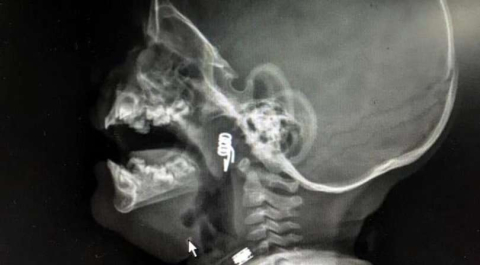

Nevşehir'de 1 yaşındaki erkek bebek Ö.Y., dün akşam saatlerinde elinde mandalla oynarken, parçalanan mandalın yayını ağzına aldı. Durumu fark eden baba hemen müdahale etti ancak yay yay bebeğin genzine kaçarak saplandı. Bunun üzerine aile hemen hastanenin yolunu tuttu. Nevşehir Devlet Hastanesi Acil Polikliniği'ne getirilen bebeği, Acil Nöbetçi doktoru Mustafa Alpaslan muayene ederek gerekli tetkikleri yaptı. Çekilen röntgen filmlerinde mandal yayının lokalizasyonu ve durumu belirlendi. Daha sonra, KBB Uzmanı Op. Dr. Ahmet Cevatzade tarafından yapılan başarılı ameliyat sonucunda bebeğin genzine saplanan mandal yayı çıkartıldı.